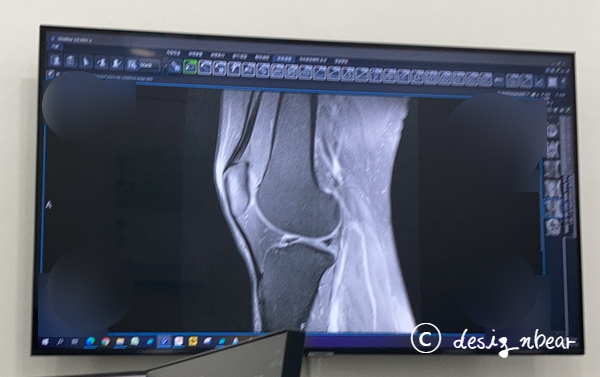

한 해가 가기 전 병원